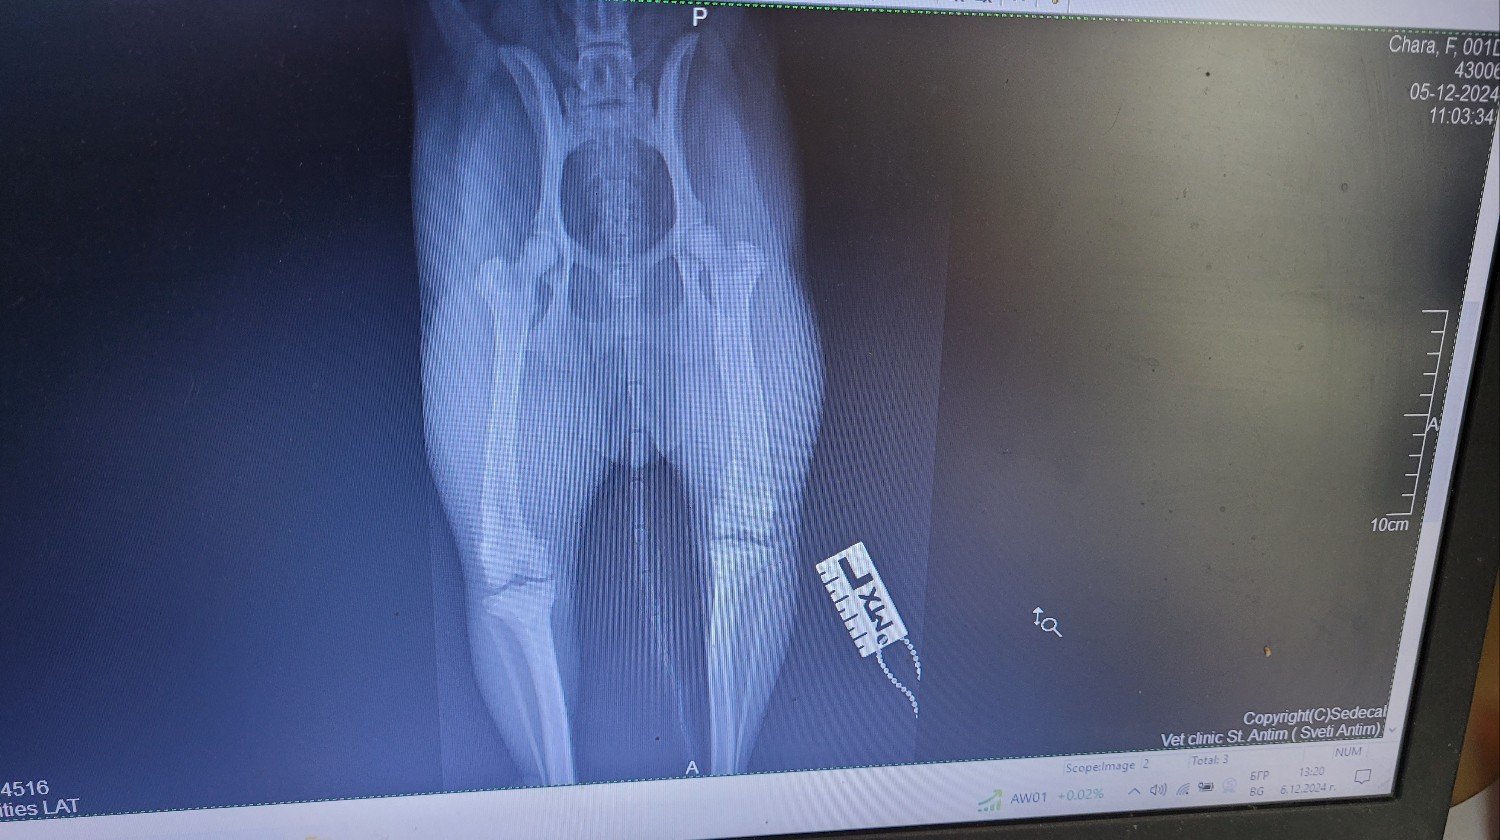

Ora è con noi da 3 mesi e oggi dovevamo fare una radiografia alle zampe e alla colonna vertebrale, poiché a volte zoppica leggermente con la zampa posteriore sinistra e mostra lievi segni di dolore.

È emerso che all'età di 1 o 2 mesi aveva una frattura alla zampa posteriore superiore che è guarita in modo non ottimale senza alcun trattamento. Di conseguenza, l'osso è un po' più corto e un po' curvo e il tendine esterno del ginocchio è allentato, per cui la sua rotula va verso l'interno della gamba. Questa situazione deve essere corretta con un intervento chirurgico, poiché il cane è ancora molto giovane e diventerà un handycapped molto presto nella sua vita. Al momento ha circa 8 mesi.

Non posso caricare molto qui, ma potete controllare il mio account TikTok Shushka1781 per vedere altre cose di Chara e Kalina-Bubka. Cercherò di caricare le radiografie in modo che possiate vederle.